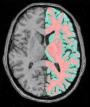

Trigger all segmentation tools for T1-weighted data

This pipeline is now named "Morphologist", and is the main entry point of the "Morphologist" toolbox dedicated to the processing of T1 MRI data. It is the evolution of the older "T1 Pipeline".

In Morphologist 2012, the first steps of the pipeline (bias correction, histogram analysis, brain segmentation, hemispheres separation) have been clean up. Now there is only one choice for each step. Furthermore the grey/white interface has undergone significant improvements, making the grey/white surface consistent with the grey/white classification and meshes have been also improved, making them less decimated and more precise to the mask.This pipeline allows to compute:

A pipeline normally deals with both hemispheres, but can be asked to process only one. Processing steps are executed in the following order (except when some results have already been validated/locked or unchecked in the graphical interface) :

- Ensure image orientation and reorient it if needed (Prepare Subject for Anatomical Pipeline) ;

- Computation of a brain mask (Brain Mask Segmentation) ;

- Computation of a mask for each hemisphere (Split Brain Mask) ;

- A grey/white classification of each hemisphere to perform "Voxel Based Morphometry" (Grey White Classification) and spherical triangulation of cortical hemispheres (Grey White Surface) ;

- Spherical triangulation of the external interface of the cortex of one or two hemispheres (Get Spherical Hemi Surface) ;

- Computation of a graph representing the cortical fold topography (Cortical Fold Graph) ;

- Possibly, automatic identification of the cortical sulci (Automatic Sulci Recognition), located in the "sulci" toolbox.